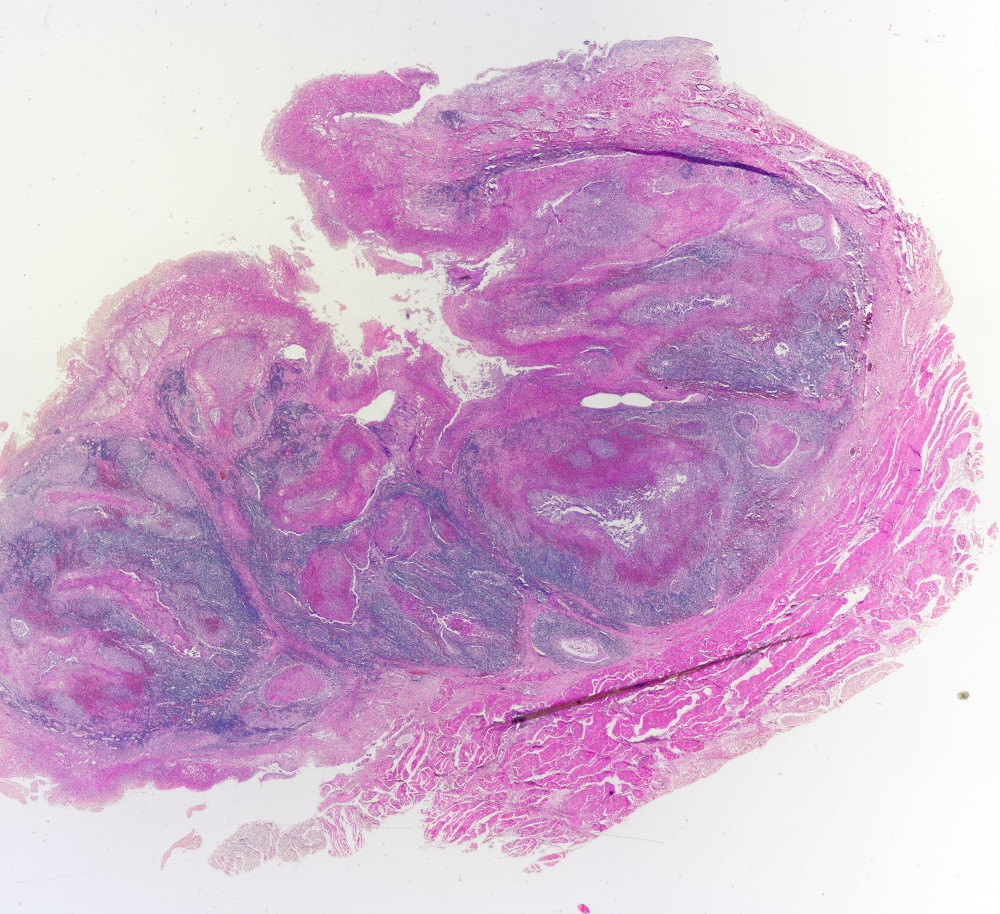

Abb.8  Diphtherie der Gaumenmandel. Übersicht. Sammlungspräparat. Leitz PL 1,6;

Abb. 9  Übersicht, mit Erläuterungen. A Pseudomembran; B unverändertes Epithel; C Tonsillarbucht, von Pseudomembran ausgefüllt; D tiefere Nekrosezone; E lymphatisches Gewebe der Tonsille. Die intensiv rot hervortretenden Areale sind Nekrosen.